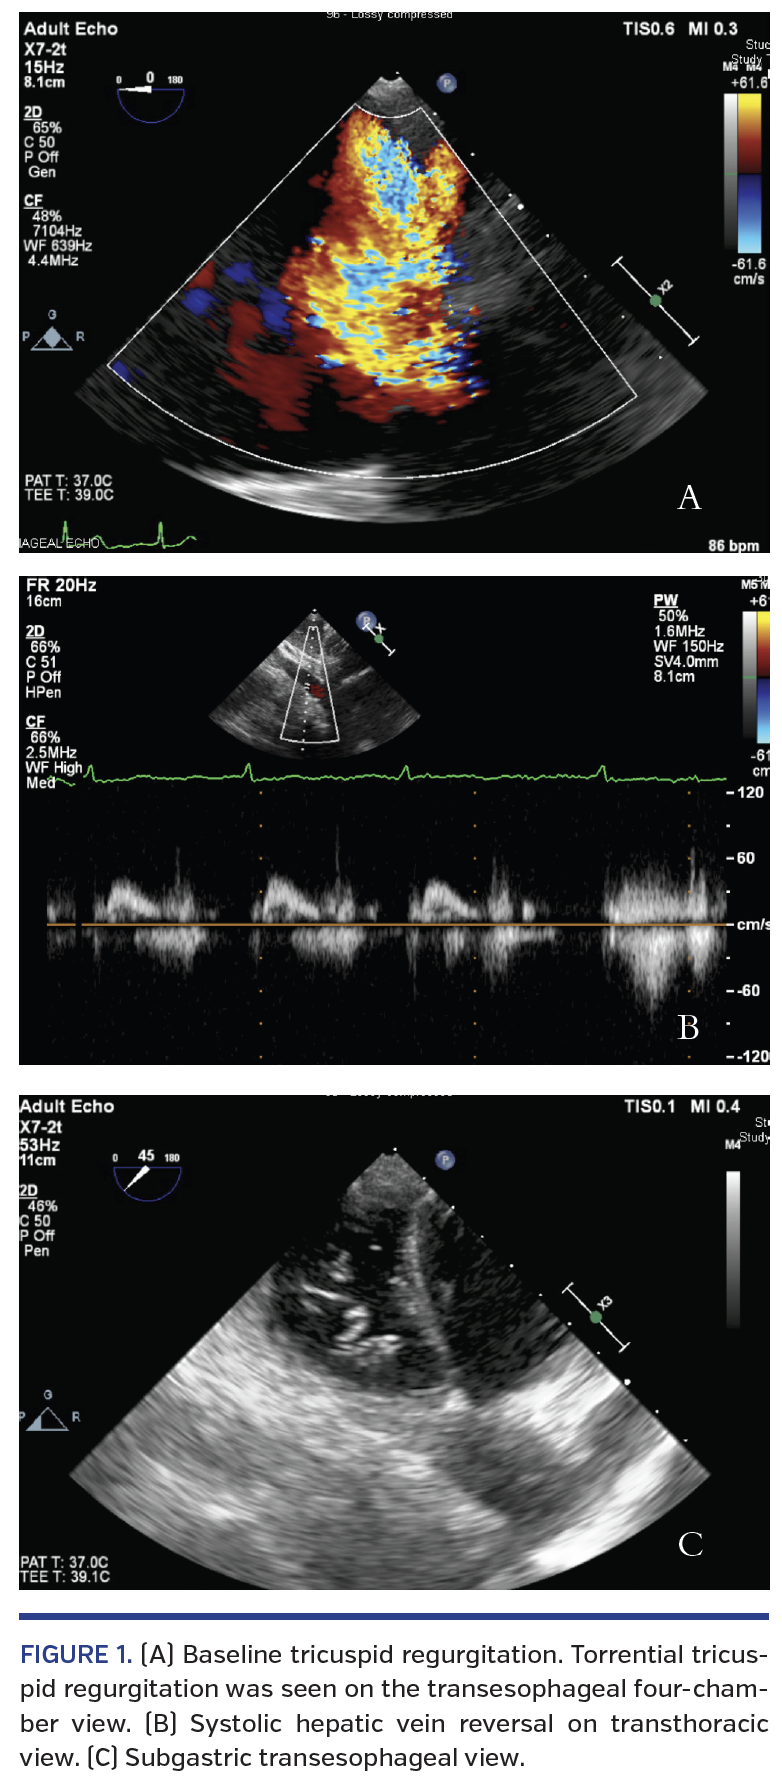

A 77-year-old female with severe symptomatic mitral and tricuspid regurgitation was referred for valve surgery. She had significant shortness of breath with New York Heart Association class IV symptoms, orthopnea, and persistent edema refractory to diuretic therapy. She was unwilling to perform a 6-minute walk test due to dyspnea and had additional history of breast cancer treated with a radical left mastectomy with radiation, cachexia (body mass index, 16.8 kg/m2), emphysema, atrial fibrillation, and frailty (5-meter walk test >5 seconds). Transthoracic echocardiography showed moderate aortic insufficiency, severe myxomatous mitral regurgitation with flail anterior leaflet and posterior jet, in addition to torrential tricuspid regurgitation (Figure 1). After extensive discussion among our institutional heart team, the patient was felt to be at prohibitive risk for surgery and a candidate for percutaneous transcatheter mitral valve repair. The patient was offered concomitant percutaneous tricuspid valve repair. After discussion of the risks and benefits with the patient and her family, she elected to undergo transcatheter repair for both mitral and tricuspid valve regurgitations.

The patient was intubated and sedated. A transesophageal echocardiographic (TEE) probe was inserted. After successful transseptal puncture, percutaneous mitral valve repair was performed with the MitraClip device (Abbott Vascular) using two clips, decreasing mitral regurgitation to mild with a resting mean mitral valve gradient of 5 mm Hg. The MitraClip delivery guide was withdrawn to the level of the right atrium.